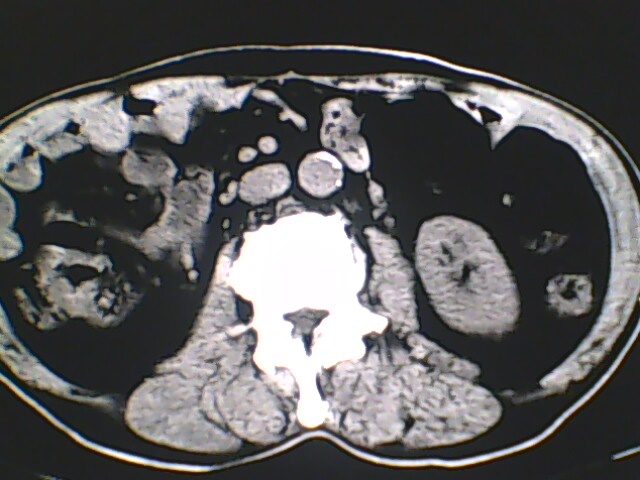

男,56岁,高血压,临床怀疑肾上腺问题,肝脏怎么那么高啊?能描述一下么?

右侧膈膨升,间位结肠,胸腰椎退行性骨关节病,右侧肾上腺可疑增生(图像颗粒太粗,窗太窄,不好看)。

支持 右侧膈膨升,间位结肠;胸腰椎退行性骨关节病;双侧肾上腺可疑增生。